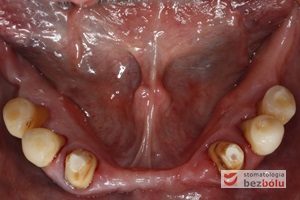

Żuchwa - widok powierzchni okluzyjnej - symetryczne braki zębowe w zakresie 4 siekaczy i trzonowców

Żuchwa – widok powierzchni okluzyjnej – symetryczne braki zębowe w zakresie 4 siekaczy i trzonowców